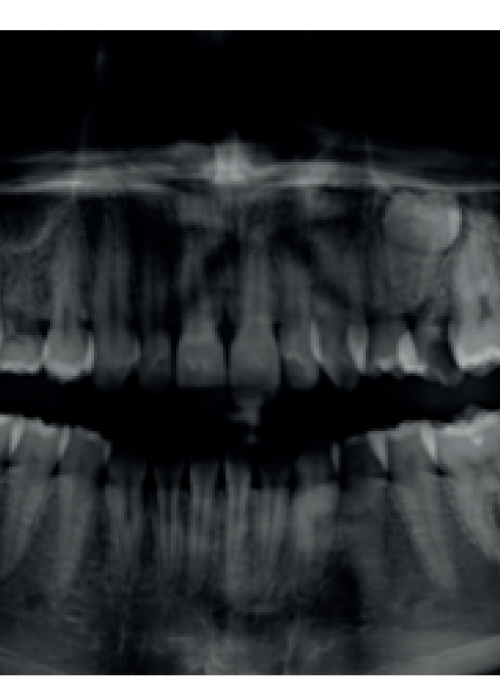

Regeneración ósea guiada con dentina autógena tras la exodoncia de un premolar retenido en posición invertida: evaluación a 4 meses de un caso clínico